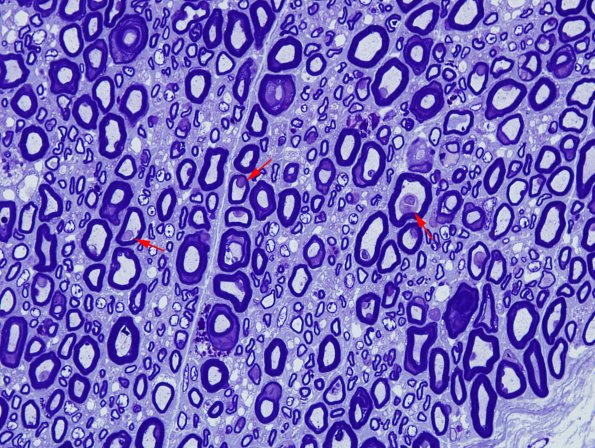

Notice the numerous macrophages within the myelin sheathes adjacent to the largely preserved axons. (Plastic sections)